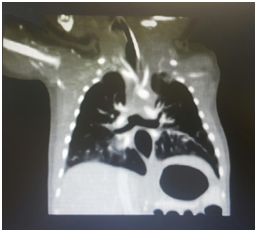

At day three of life, patient was transferred to our hospital for further management. Patient was kept on CMV mode with persistence of his CO2 retention. Echocardiography done showed ASD Ostium Secundum 8mm with left to right shunt and pulmonary hypertension (PAP=30mmHg). A bedside Fibroscopy was done revealing a blunted end suspecting tracheal agenesis. Computerized tomography scan (CT scan) confirmed the diagnosis of tracheal agenesis: the trachea extends for a distance of 1cm after which it completely obliterates. A fistula connecting the larynx and the esophagus at the level of the vocal cords and another fistula separating the esophagus and the carina were noted (Figure 1).

Figure 1 A fistula connecting the larynx and the esophagus at the level of the vocal cords and another fistula separating the esophagus and the carina were noted.